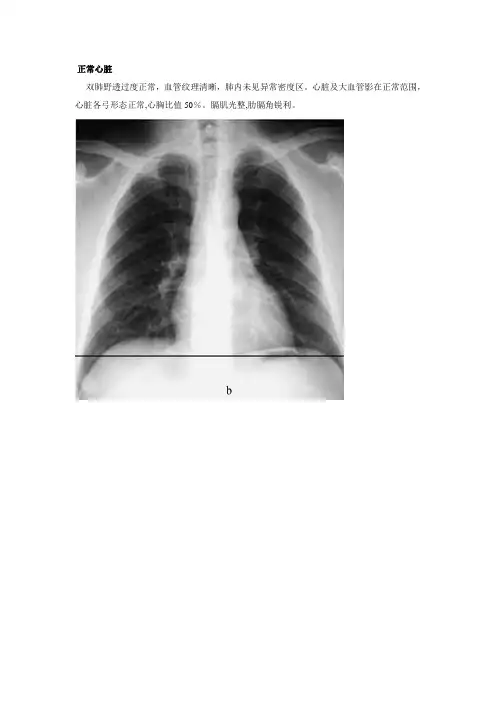

正常心脏双肺野透过度正常,血管纹理清晰,肺内未见异常密度区。

心脏及大血管影在正常范围,心脏各弓形态正常,心胸比值50%。

膈肌光整,肋膈角锐利。